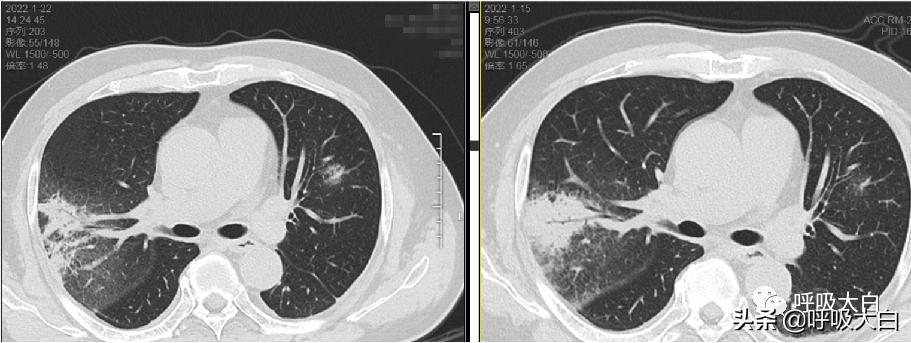

肺部影像学表现为不同程度渗出、实变,为胸膜下淡薄阴影,密度不均,病变呈扇形,肺部炎性浸润伴间质性炎症,单侧下肺叶节段实变多见,双侧实变、多发结节样或粟粒样浸润在部分患者可见,胸腔积液及肺门淋巴结病少见。

2-其他病例胸部CT

治疗前 治疗后